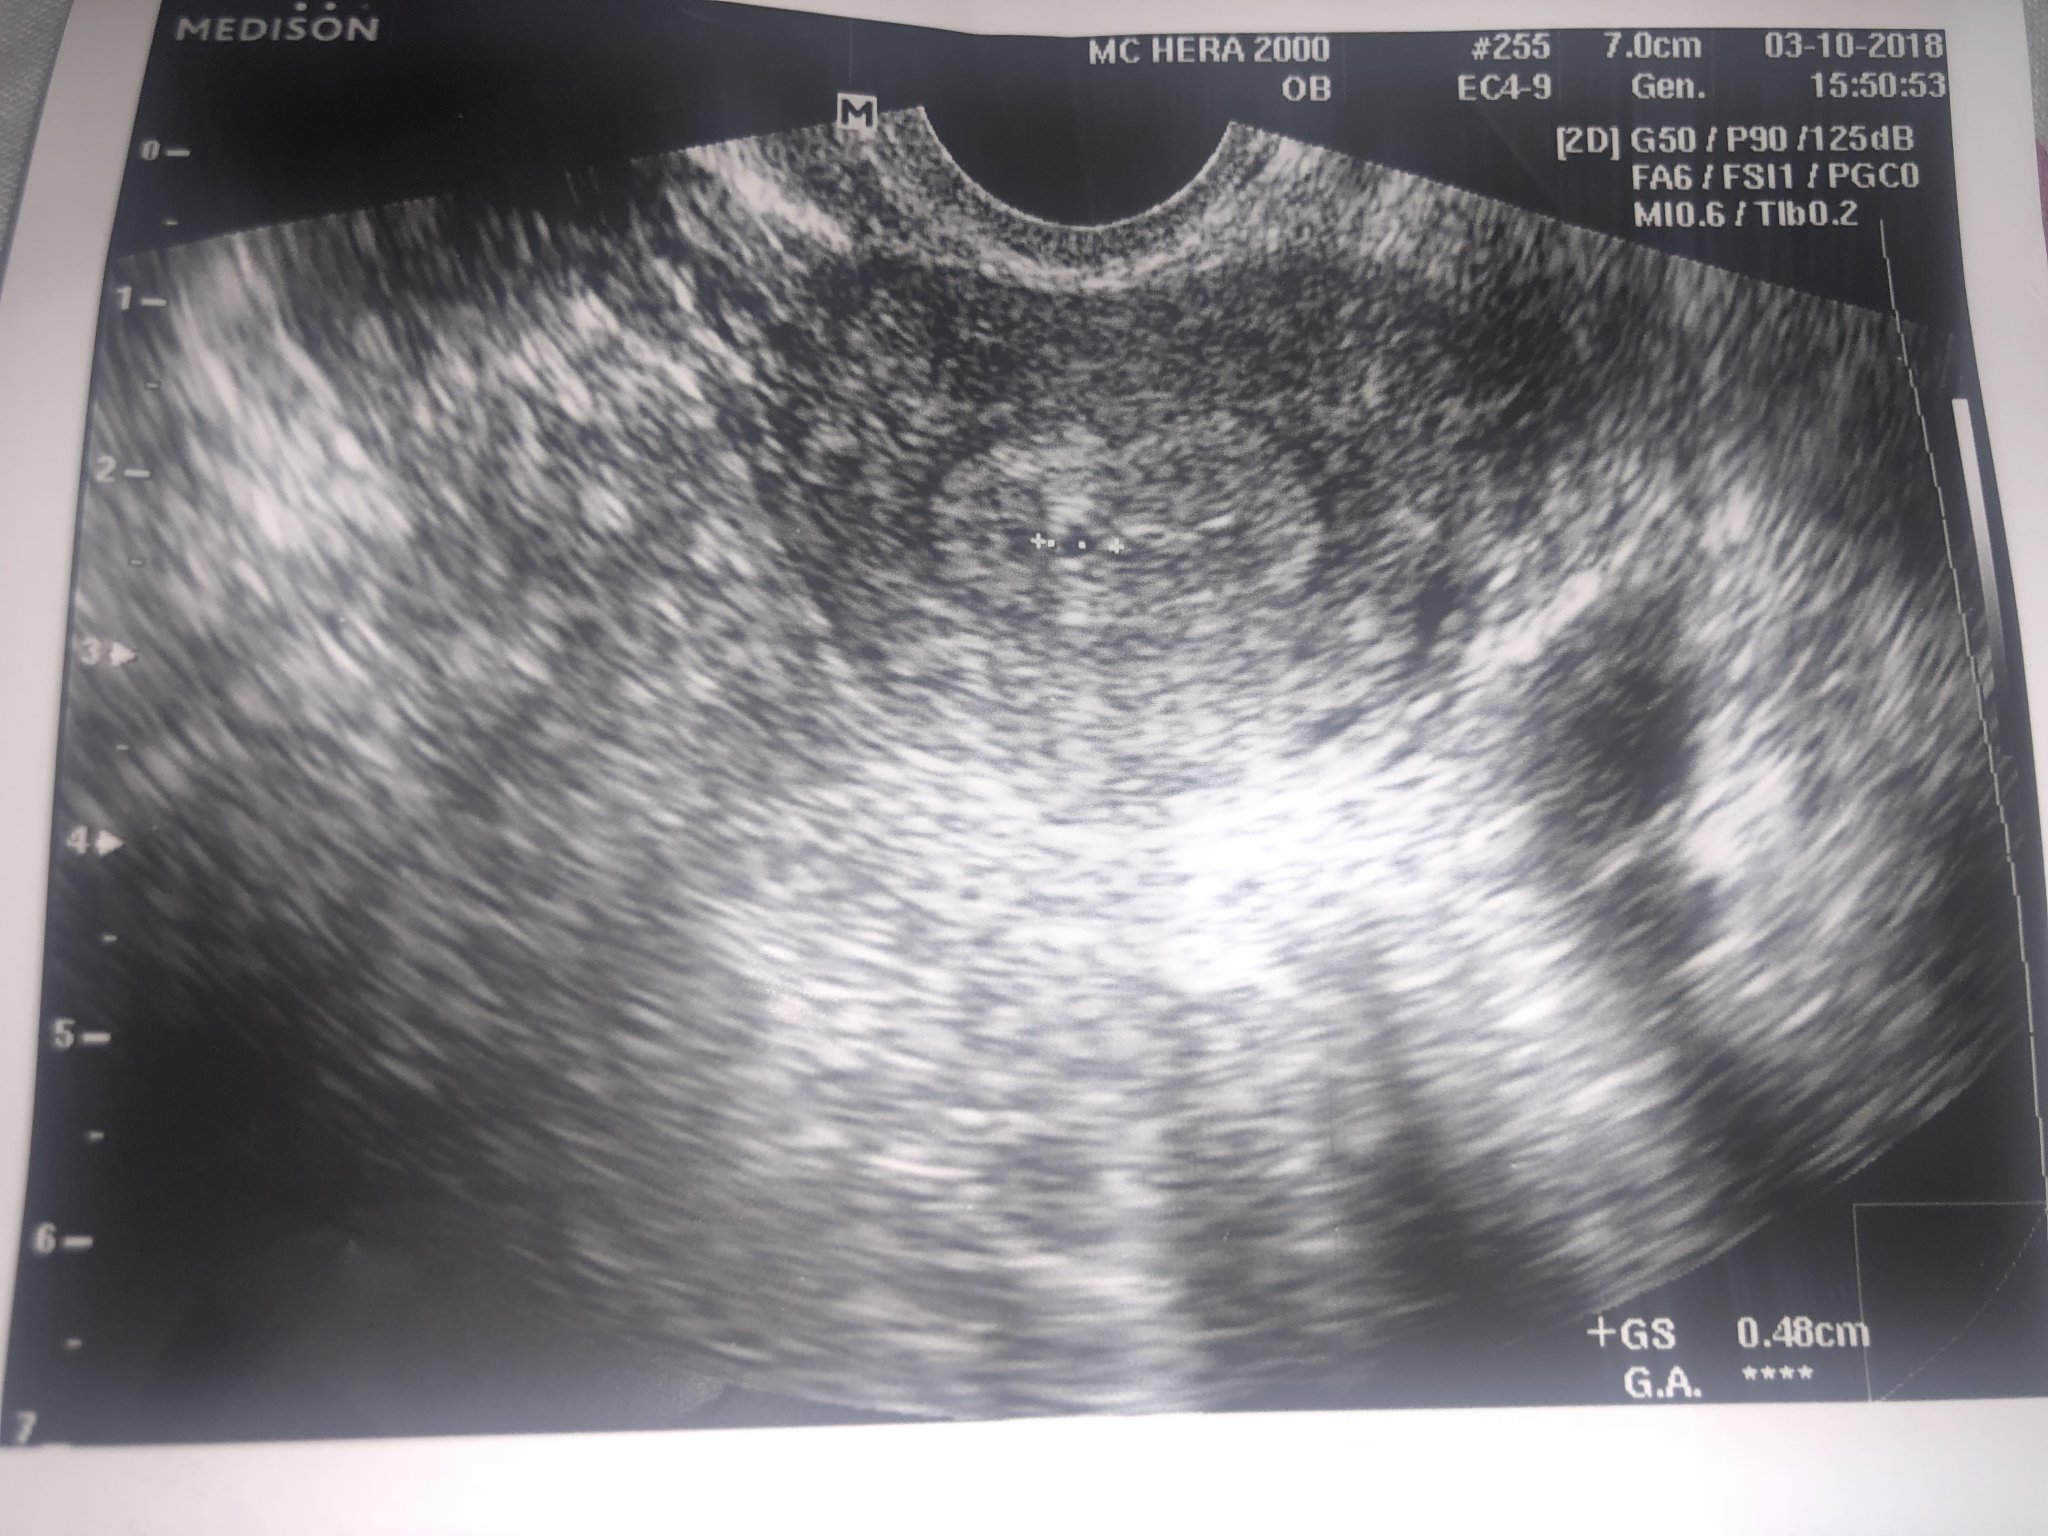

Маркирала го е като 0,48см ....

Това е от днес ... след кървенето .

Виж не искам да те плаша.. Но аз края на 2016г. имах такъв проблем.. Смисъл моето беше кухо яйце.. Ходих на лекар, не помня в коя седмица, но се предполага ще, че в тази седмица вече трябва да има сърдечен ритъм, такъв нямаше.. Но АГ-то каза, че ще изчакаме, защото не може да е 100% сигурен, че е кухо яйце и ми изписа дуфастон 3×1, но още на другия ден започнаха леки болки, кафеникаво зацапване.. И се чухме с лекаря и каза да отидем и аз влязох да си взема душ и падна едно малко съсипе че, което всъщност е било празната яйцеклетка и така всичко приключи с кюртаж..